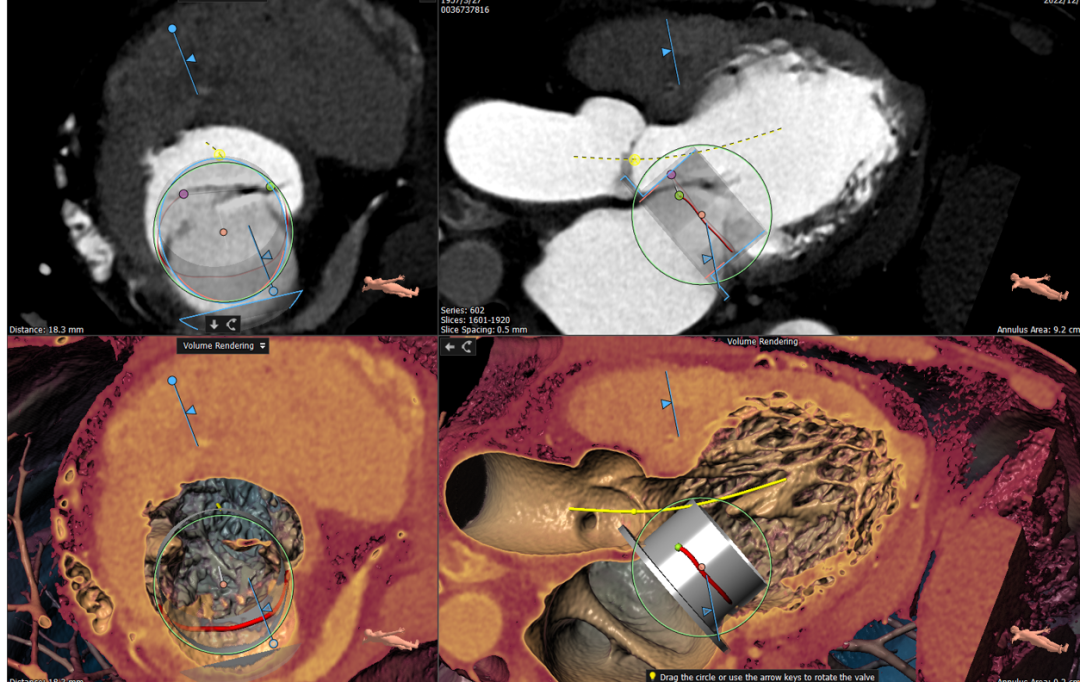

经华西医院心外科MDT团队综合评估,该患者为老年重度FMR患者,考虑外科瓣膜置换手术风险极高,决定进行MitraFix®经心尖二尖瓣植入。术前心脏CTA瓣环面积折算最大直径37 mm 模拟植入34号二尖瓣瓣膜, 收缩末心室Neo LVOT面积约230mm²。

术前瓣环形态评估

手术采用左侧第六肋间微创5cm切口心尖入路,在超声引导下,清晰识别MitraFix®输送系统准确跨瓣,并将人工瓣膜准确释放于二尖瓣瓣环,瓣膜释放后支架贴合牢固,术后无反流,二尖瓣前向血流通畅、跨瓣压差3mmHg,左心室流出道通畅,流出道血流速度为1.0m/s. 后顺利撤出输送系统,关闭心尖切口,手术顺利结束。